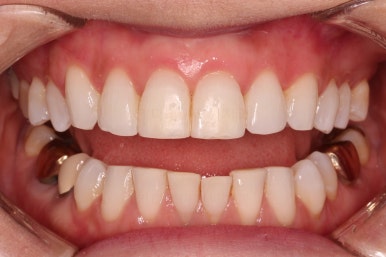

초진 시 입안의 모습입니다.

환자분이 원하셨던 부분은 윗니 작은 앞니가 하나 튀어나와서 개선하고 싶어하셨습니다.

부가적으로 아랫니 앞니가 마모가 심하여 높낮이가 달라보이는 점이었는데요.

초진 시 얼굴 모습입니다.

전반적으로 모두 양호합니다. 입이 편안하게 다물어지는 느낌, 옆라인, 심지어는 중앙선까지 양호합니다.

단 하나, 작은 앞니 하나가 톡 튀어나와 있는 부분이 미적으로 좋지 못한데요.